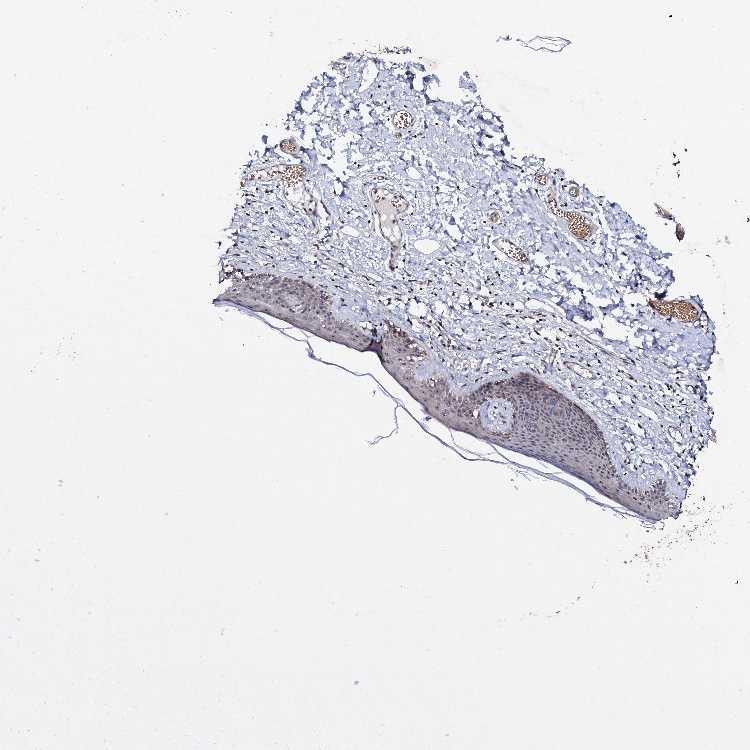

SKIN 2 - Antibody stainingi

Antibody staining in the annotated cell types in the current human tissue is reported as not detected, low, medium, or high, based on conventional immunohistochemistry profiling in selected tissues. This score is based on the combination of the staining intensity and fraction of stained cells.

Each image is clickable and will lead to virtual microscopy that enables deeper exploration of all samples and also displays staining intensity scores, fraction scores and subcellular localization as well as patient and tissue information for each sample.

Antibody HPA039618

Epidermal cells High